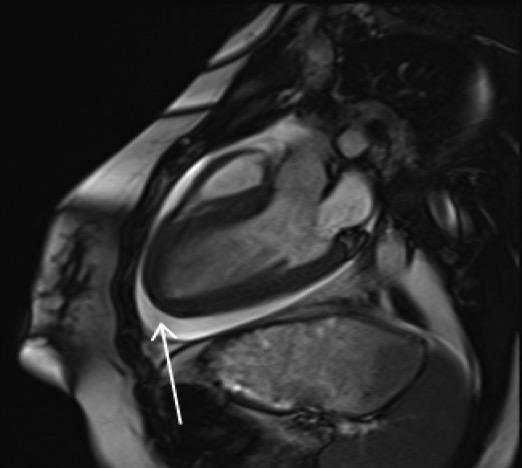

On presentation, she was hypotensive with mildly elevated lactate, troponin, and BNP, and an unremarkable ECG and chest radiograph. Initial echocardiogram showed normal LV function. Cardiac MRI revealed a pericardial effusion and increased myocardial wall enhancement. Infectious and rheumatologic workup was notable only for Parainfluenza 1 on nasal swab.

Over the next 24 hours her condition significantly worsened. She developed multi-organ failure including cardiogenic shock, transaminitis, renal insufficiency, and altered mental status requiring intubation and vasopressors. There was a rapid increase in pericardial fluid causing tamponade and she underwent an emergent pericardial window procedure. She was subsequently placed on extracorporeal membrane oxygenation (ECMO) for rapid deterioration in cardiac function with an ejection fraction of 15% despite optimal inotropic support.